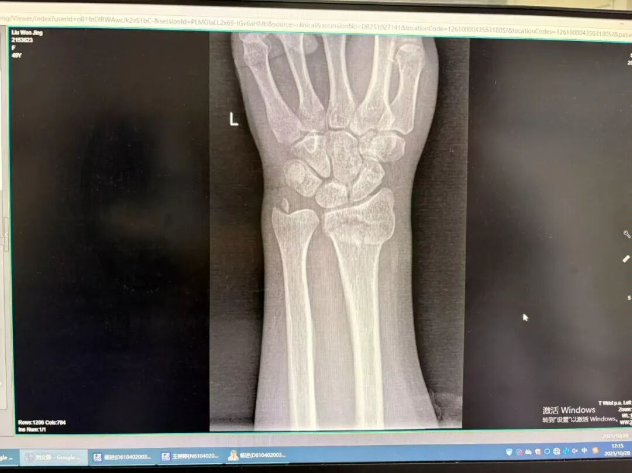

(骨折图示)

如果骨折是稳定的、没有明显移位的(比如青枝骨折),或者经过手法复位后对位良好、非常稳定的—— 我会优先考虑小夹板。 它的“动静结合”理念能让你在康复早期就开始活动,最大程度保留功能,体验感更好,恢复更快。

如果骨折是粉碎的、不稳定的、或者复位后容易再移位的 —— 那我必须请出石膏这位“镇山太保”。 此时,坚固的固定是第一要务,必须先确保骨头在一个良好的位置上长起来。